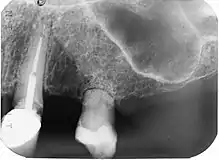

| Post traumatic External tooth resorption 9 | |

External resorption is the loss of tooth structure from the external surface of the tooth and is further subcategorized based on its etiology.[16]

External Replacement Root Resorption

External replacement root resorption (ERRR) occurs due to replacement of the root surface with bone, i.e. ankylosis. ERRR can be further categorized as transient or progressive depending on the extent of periodontal ligament damage with the latter resulting in complete root resorption.[16]